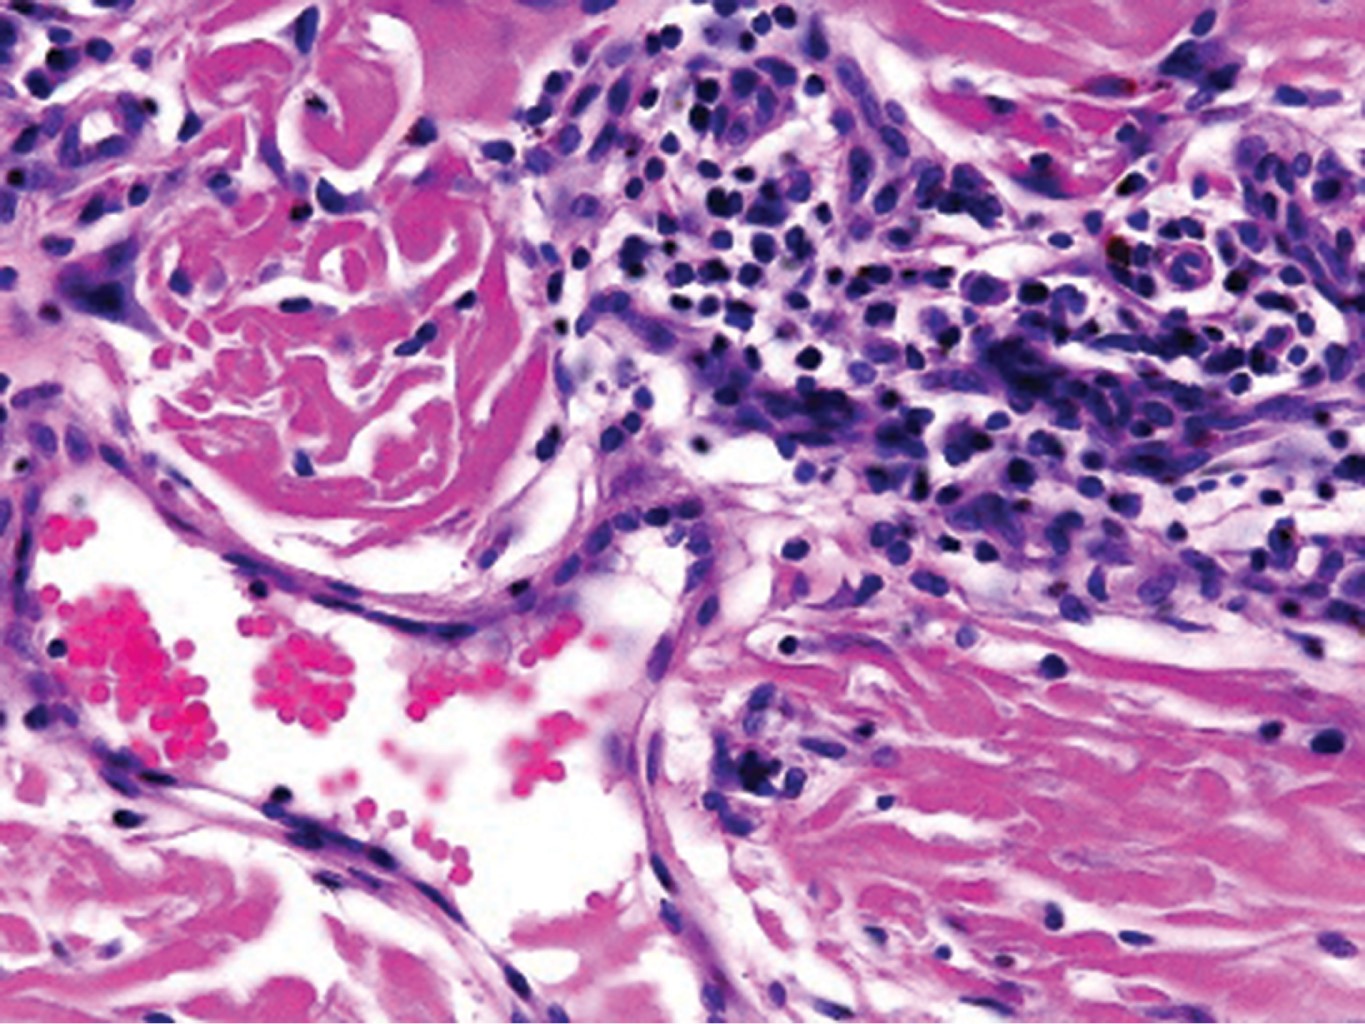

El estudio histológico es diagnóstico con los siguientes hallazgos: proliferación de vasos capilares y vénulas en la dermis superficial y media, cuyo endotelio es prominente y en ocasiones protruye hacia la luz, células multinucleadas que presentan citoplasma angulado con núcleos hipercromáticos en número variable, inmersas en un estroma fibroso.10,11 En la inmunohistoquímica, como es esperado, las células endoteliales expresan factor VIII, CD31 y CD34, mientras que los macrófagos, histiocitos y células multinucleadas expresan factor XIIIa, CD68 (variable) y vimentina.5 La dermatoscopía hasta el momento es inespecífica.12

Al interrogatorio, refiere haber iniciado hace cuatro años con "lunares" de forma lenta y progresiva. Sin tratamiento previo ni antecedentes médicos de relevancia. Clínicamente se hizo el diagnóstico de sarcoma de Kaposi vs histiocitosis y se solicitaron estudios paraclínicos, que descartaron infección por VIH u otras alteraciones. El estudio histológico mostró epidermis normal y en la dermis superficial y media presencia de vasos dilatados, fibrosis y células multinucleadas basofílicas con bordes angulosos (Figuras 3, 4 y 5).